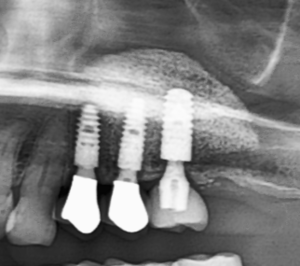

インプラント治療を終えてから20年間経過した長期経過症例です。

残存歯の予後を考慮して増骨しておくと、患者自身の身体的負担、経済的な負担を軽減することができます。

ここまでトラブルもなく、安定して経過しています。患者自身の日々のお手入れと定期検診を欠かさず継続されて

こられたからこそ得られた結果です。